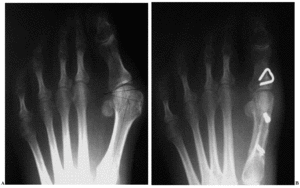

En todos los casos seguimos la técnica quirúrgica descrita por Barouk1,3,4, fijando la osteotomía diafisaria del primer metatarsiano mediante dos tornillos canulados de doble rosca. En 31 pies la corrección así obtenida no fue suficiente, por lo que se asociaron otros gestos sobre la falange proximal, como la osteotomía de Akin (21 pies) (fig. 1) o el acortamiento de la falange (10 pies). En el postoperatorio se autorizó la deambulación sin restringir la carga, colocando un calzado postquirúrgico con tacón invertido durante 4 a 6 semanas, para posteriormente emplear un calzado convencional.

Figura 1. Radiografías anteroposteriores en carga correspondientes a una mujer de 54 años con hallux valgus marcado. A: imagen preoperatoria. B: imagen postoperatoria (18 meses), en la que se aprecia la osteotomía en scarf del primer metatarsiano asociada a la osteotomía de Akin de la primera falange y las osteotomías de Weil del segundo, tercer y cuarto metatarsianos. El resultado fue satisfactorio.